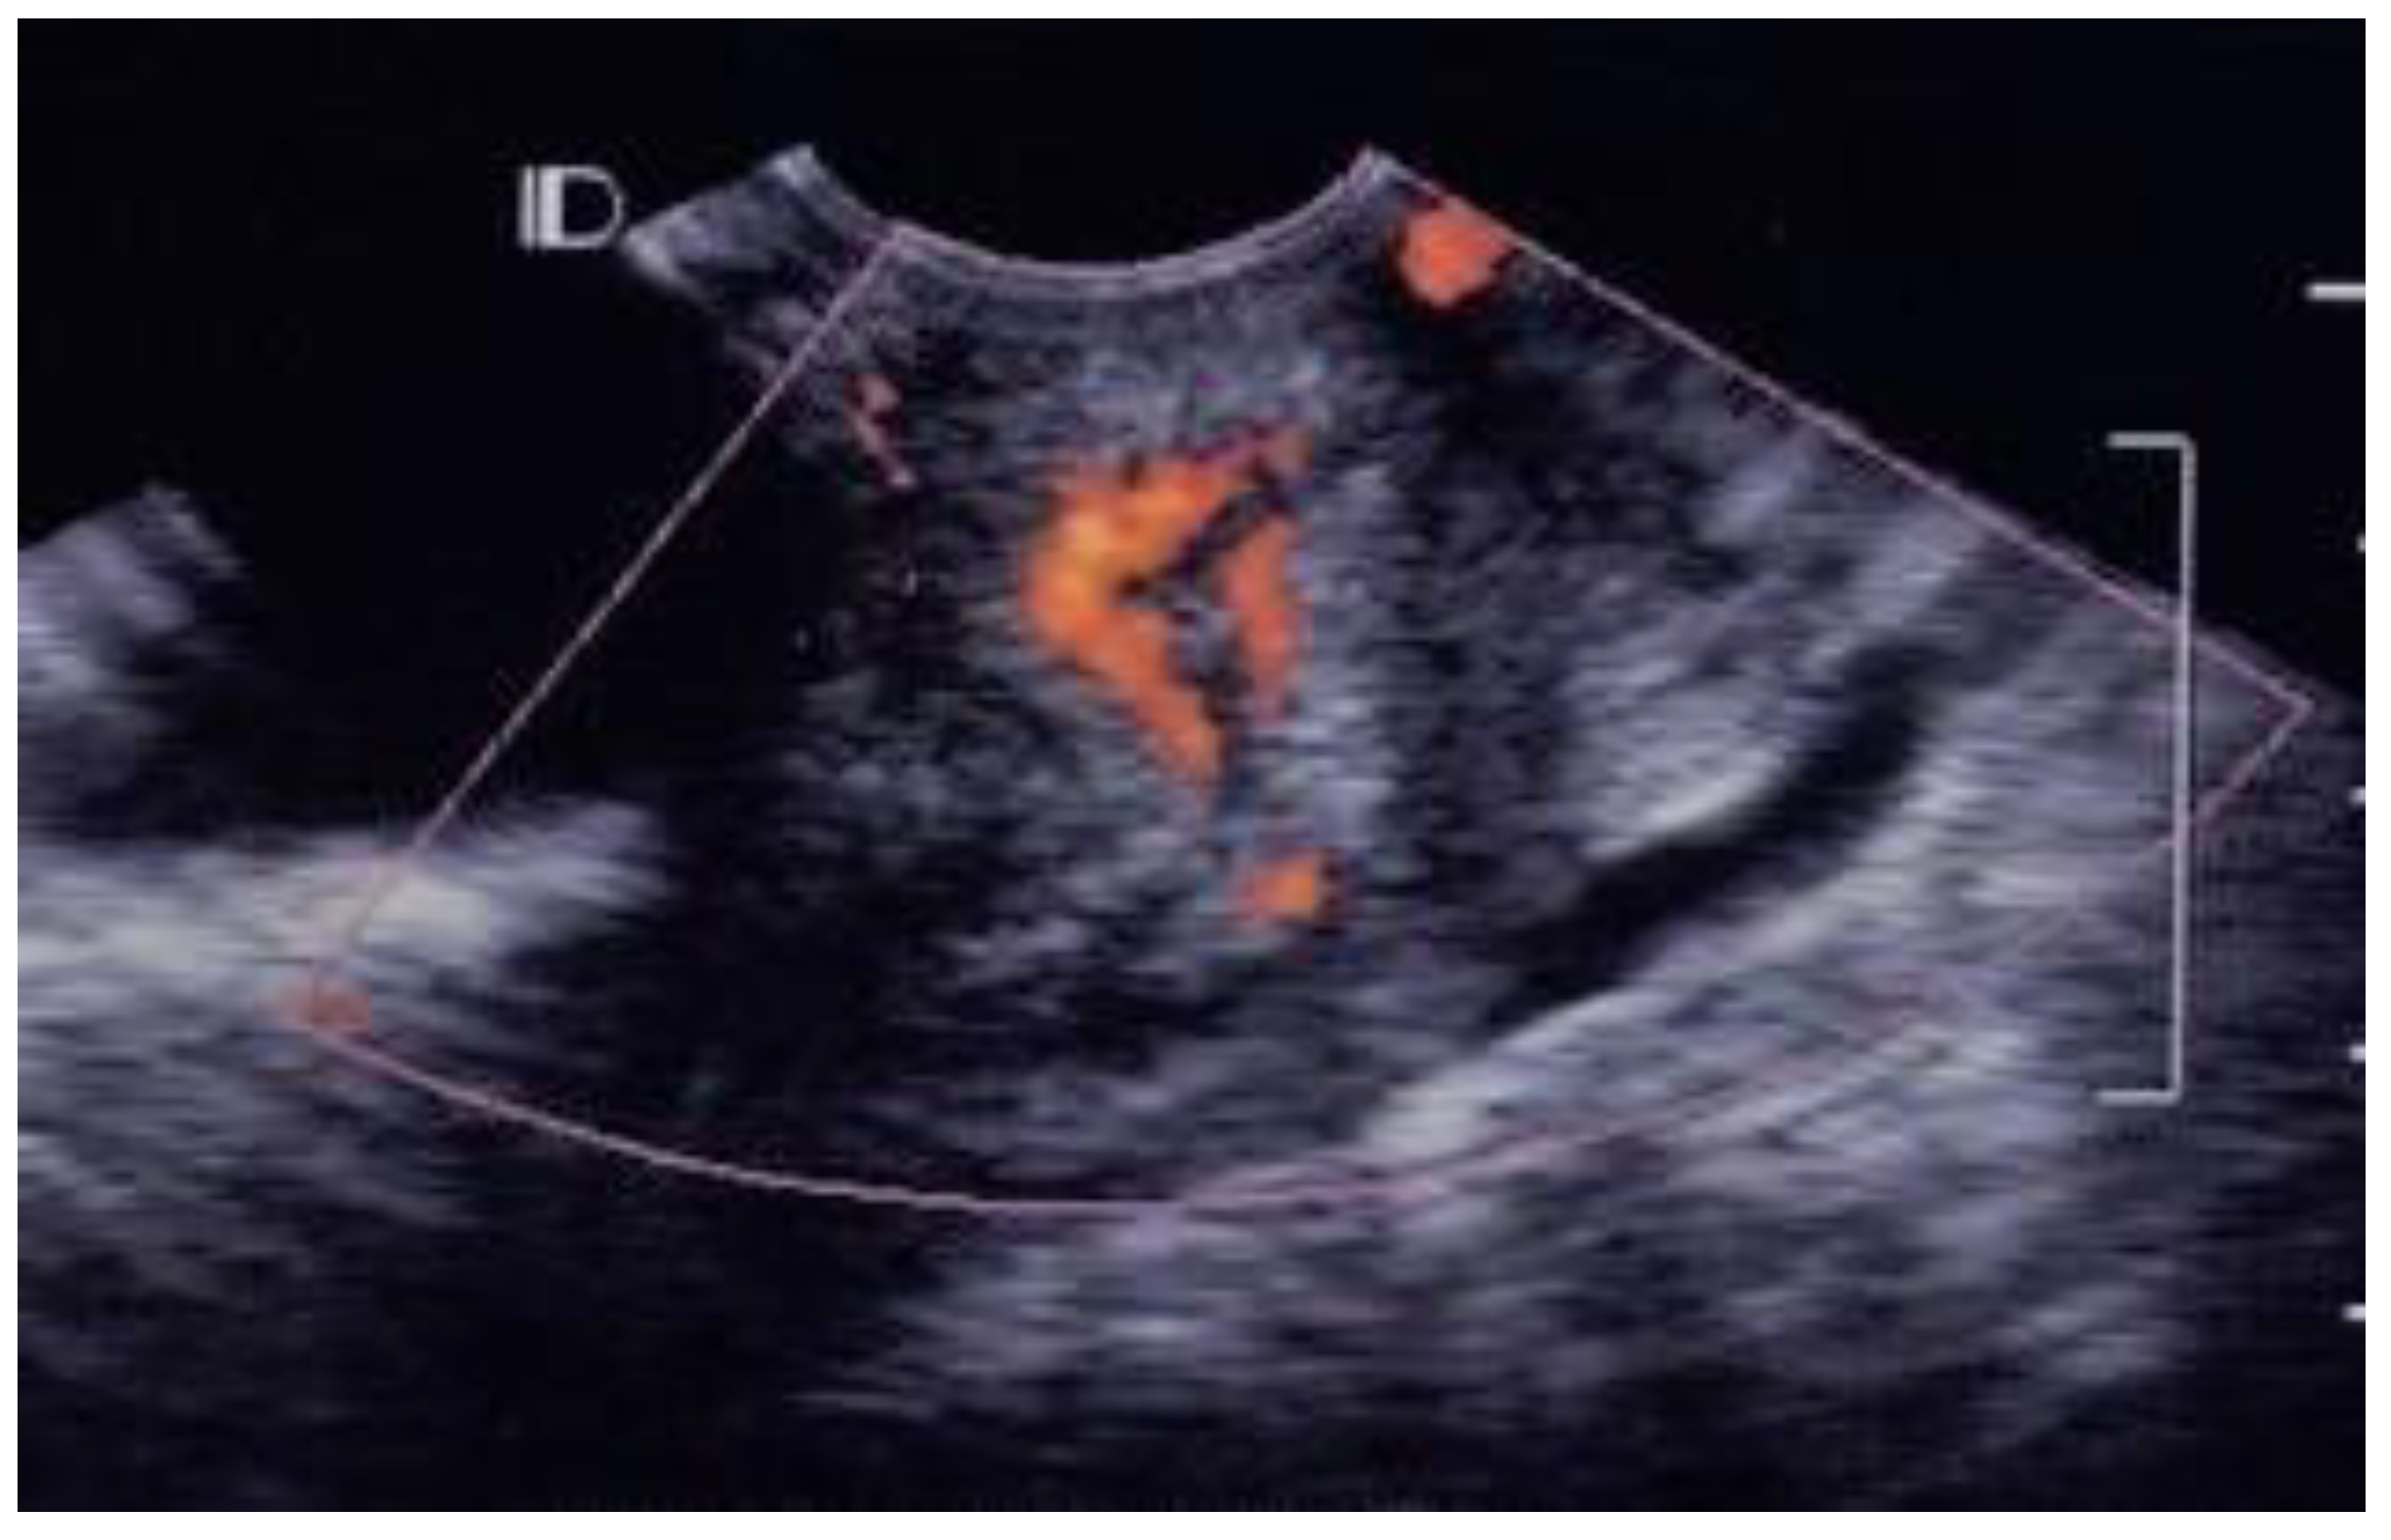

3.1. Visual Grading of Vascularity Findings on TV-PDU

| Grade 0 | Absence of vascular hot spot |

| Grade 1 | <5 vascular spots, not involve the endocervical canal |

| Grade 2 | >5 vascular spots, not involve the endocervical canal |

| Grade 3 | Involved the endocervical canal, without involved whole endocervix |

| Grade 4 | Involved the whole endocervix |